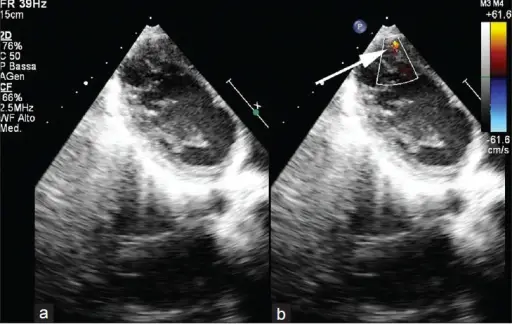

Atrial Septal Defect (ASD)

An atrial septal defect (ASD) is a hole in the wall that separates the right and left atria.

Ostium secundum is the most prevalent (90 percent of cases) cause of atrial septal defect (ASD).

Down syndrome is linked to the osteoid primum type of atrial septal defect (ASD).

An atrial septal defect (ASD) results in a divided S2 and a left-to-right shunt on auscultation (increased blood in right heart delays closure of pulmonary valve).

Paradoxical emboli are potential complications of atrial septal defects (ASD).